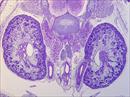

| Mutant 2459-006-1 (E16.5) shows kidneys that appear cystic and have hydronephrosis | b2b2459Clo/b2b2459Clo | C57BL/6J-b2b2459Clo |

| Mutant 2459-006-1 has moderately cystic kidneys | b2b2459Clo/b2b2459Clo | C57BL/6J-b2b2459Clo |

| Mutant 2459-003-2 (E14.5) shows cystic and dysplastic kidneys | b2b2459Clo/b2b2459Clo | C57BL/6J-b2b2459Clo |